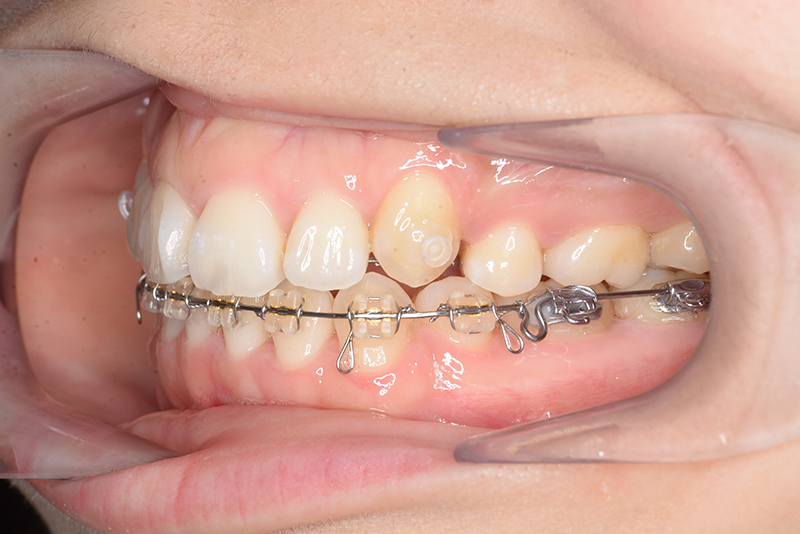

| 口腔内所見 | over jet 4.5mm、over bite 4.0mm、大臼歯関係 I級で上下顎前歯部に叢生が認められた。 |

| 批評・予后 | 叢生が大きかった影響もあり、治療期間は20ヶ月と比較的短い期間が終了できた。治療後においては口元の改善、咬合の緊密化は達成できたように思う。 |